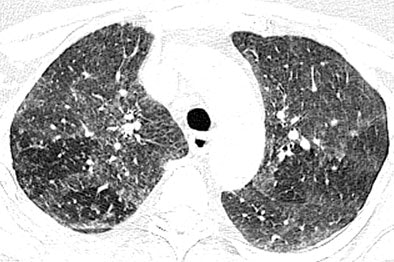

In the new pattern of pulmonary disease known as hot tub lung, "centrilobular nodules and areas of ground-glass attenuation are the most common findings, and typically have diffuse but patchy distribution throughout both lungs," Hartman and colleagues wrote. Expiratory images showed evidence of air trapping in all seven cases for which they were available, they added.

| High-resolution CT images through upper lungs in 53-year-old woman. Above, inspiratory image shows patchy areas of ground-glass attenuation bilaterally with few areas of uninvolved lung. Below, expiratory image shows air trapping in uninvolved areas of upper lungs that is more prominent on right. Images republished with permission of the American Roentgen Ray Society©, from AJR 2007; 188:1050-1053 by Thomas E. Hartmann, Eric Jensen, Henry D. Tazelaar, Viktor Hanak, and Jay H. Ryu. |

Their findings are not specific, however, and significantly, "overlap with previously reported findings of subacute hypersensitivity pneumonitis," the team wrote. "In fact, review of the initial interpretations of the CT images included in this study indicates that hypersensitivity pneumonitis was a primary diagnostic consideration in each case."